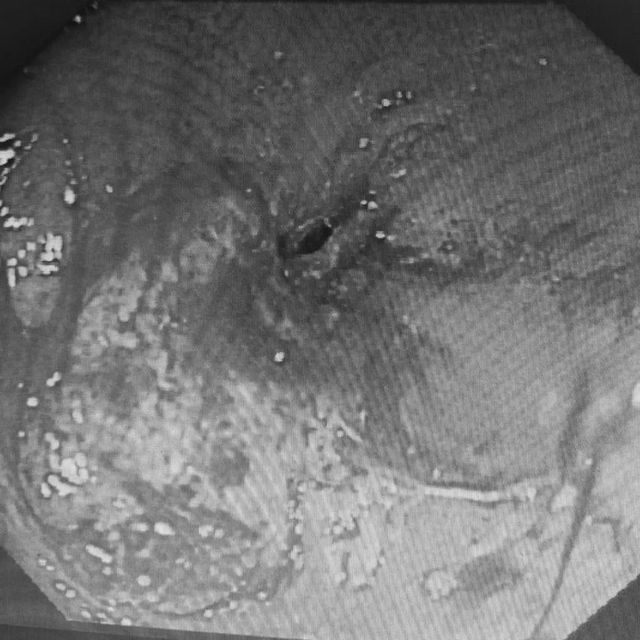

如罗晓华护士长之前判断一样

老人为食管恶性肿瘤占位,食道肿物基本已经环周,只留下了一个非常细小的管腔,正常胃镜根本无法通过,并且肿物稍微触碰摩擦就出现渗血出血的情况,并且老人身体衰弱,难度和风险很大。